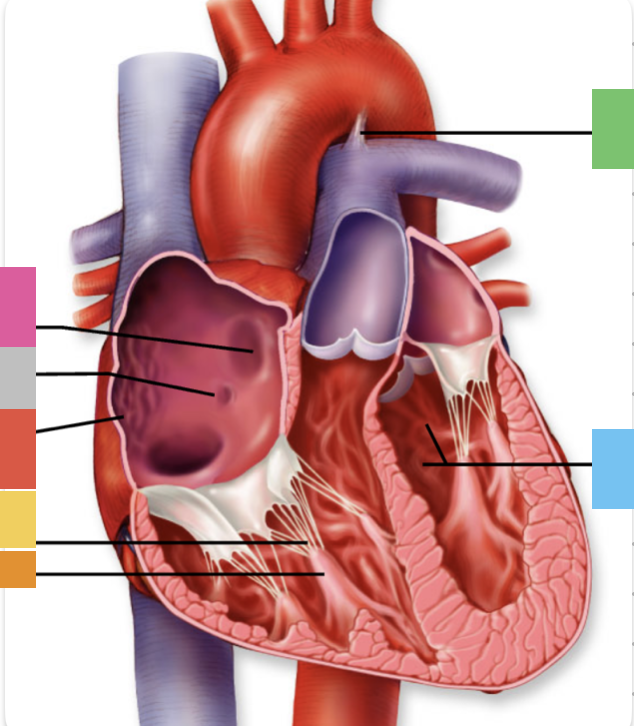

light purple

base

purple

apex

grey

right atrium

pink

right auricle

green

left atrium

green

left auricle

blue

right ventricle

orange

left ventricle

green

coronary (atrioventricular) sulcus

pink

interatrial septum

dark blue

interventricular septum

green

anterior interventricular sulcus

green

posterior interventricular sulcus

orange

aortic valve

yellow

pulmonary valve

red

tricuspid valve (right AV)

purple

bicuspid valve (left AV)

yellow

chordae tendineae

orange

papillary m.

blue

trabeculae carneae - only in ventricles

red

pectinate m. - only in R atrium

pink

fossa ovalis

grey

opening of coronary sinus